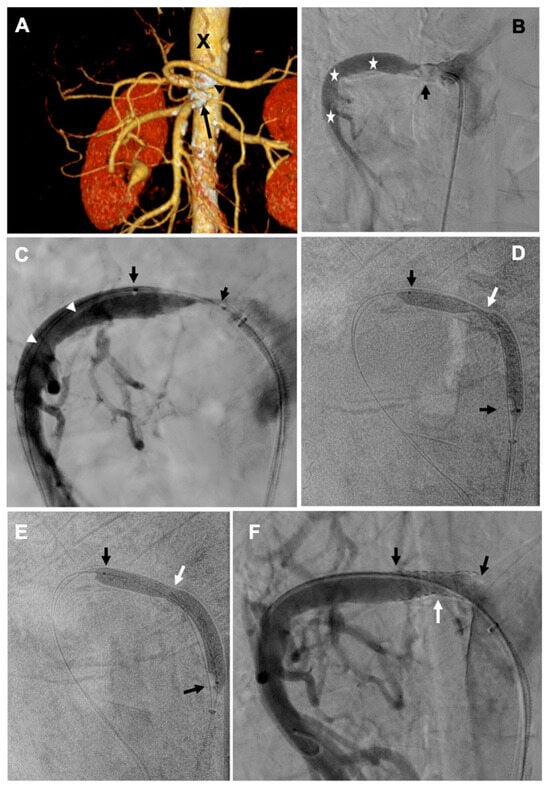

2. Case Report—Calcified Plaques in the SMA Extending to the Aortic Wall